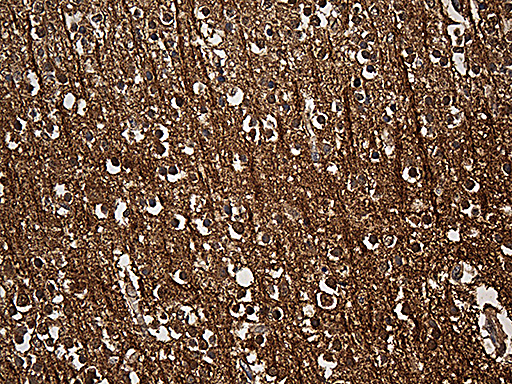

Immunohistochemical staining of paraffin-embedded Human adult brain tissue within the normal limits using anti-SNCA mouse monoclonal antibody. (Heat-induced epitope retrieval by 1mM EDTA in 10mM Tris buffer (pH8.5) at 120°C for 3min, MA00215) (1:500)